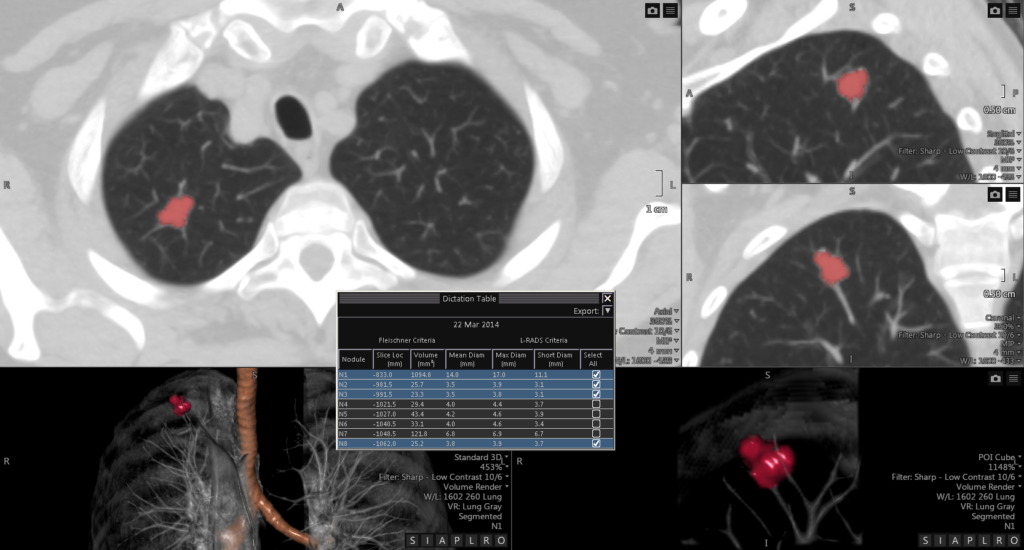

Visia™ CT Lung CAD

Visia™ CT Lung CAD is integrated into Vitrea® Advanced Visualization and facilitates time-efficient and safe radiological diagnosis of MSCT-images in clinical daily routine.